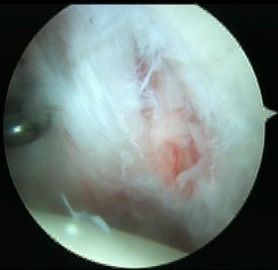

Anterior inferior labral tears |

Below equator 3 - 6 o'clock |